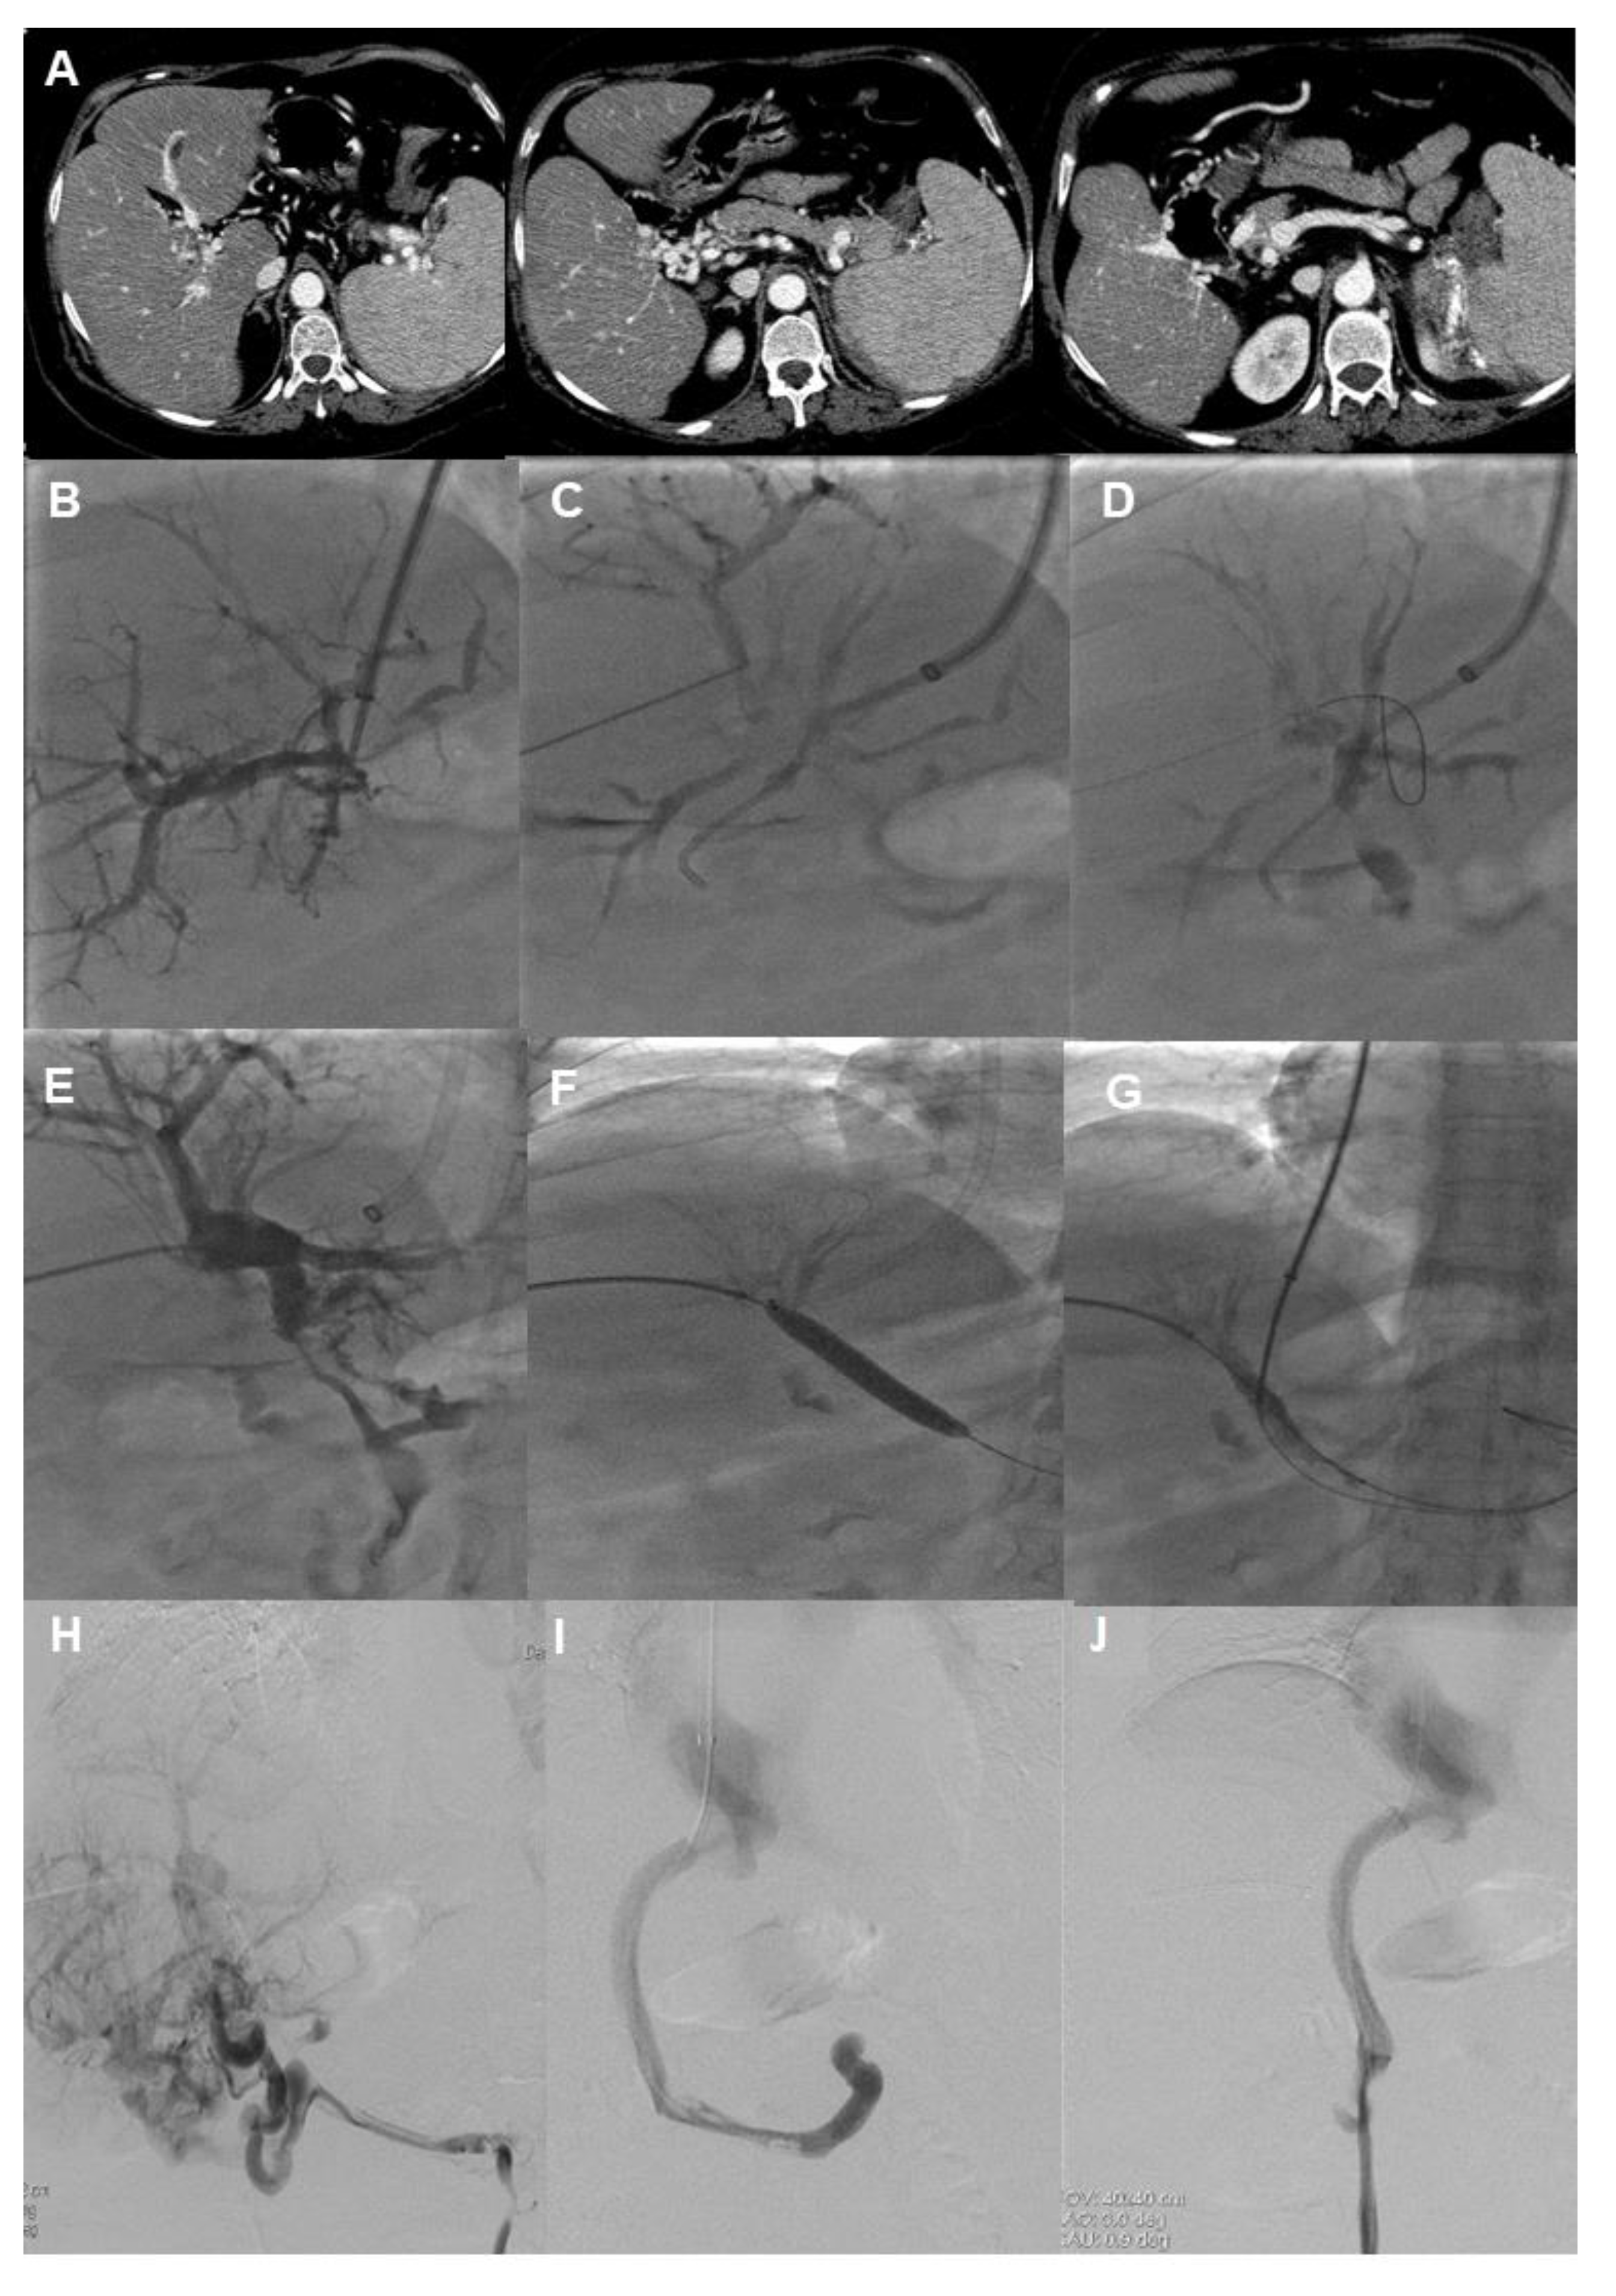

- Miraglia, R.; Maruzzelli, L.; Cannataci, C.; Gerasia, R.; Mamone, G.; Cortis, K.; Cimo, B.; Petridis, I.; Volpes, R.; Luca, A. Radiation exposure during transjugular intrahepatic portosystemic shunt creation in patients with complete portal vein thrombosis or portal cavernoma. Radiol. Med. 2020, 125, 609–617. [Google Scholar] [CrossRef]

- Chen, Y.; Ye, P.; Li, Y.; Ma, S.; Zhao, J.; Zeng, Q. Percutaneous transhepatic balloon-assisted transjugular intrahepatic portosystemic shunt for chronic, totally occluded, portal vein thrombosis with symptomatic portal hypertension: Procedure technique, safety, and clinical applications. Eur. Radiol. 2015, 25, 3431–3437. [Google Scholar] [CrossRef]

- Klinger, C.; Riecken, B.; Schmidt, A.; De Gottardi, A.; Meier, B.; Bosch, J.; Caca, K. Transjugular portal vein recanalization with creation of intrahepatic portosystemic shunt (PVR-TIPS) in patients with chronic non-cirrhotic, non-malignant portal vein thrombosis. Z. Gastroenterol. 2018, 56, 221–237. [Google Scholar] [CrossRef]